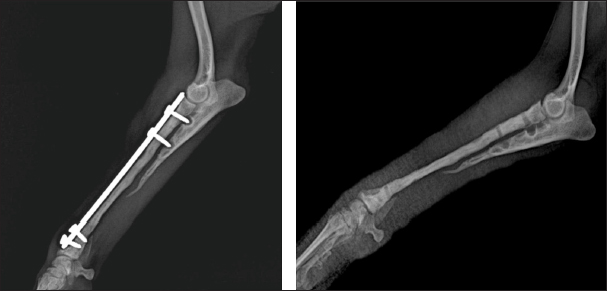

One month after the second osteosynthesis, the dog was brought for an orthopedic examination with high-grade lameness in the right thoracic limb, swelling, and severe pain in the distal part of the antebrachium. Clinical examination, complete blood counts, and serum biochemical profile revealed no abnormal findings. After deep sedation with 0.075 mg/kg medetomidine hydrochloride (Dorbene vet®, 1 mg/ml, Syva, Spain) and 7.5 mg/kg ketamine hydrochloride (Anaket®, 100 mg/ml, Richter Pharma, Austria), applied intramuscularly in the quadriceps femoris muscle, a mediolateral radiograph was made (Philips, Bucky Diagnost CS4, Holland; exposure data 50 kV, 10 mAs). The radiograph demonstrated osteolytic areas around the fixation elements, part of a broken Kirschner wire in the proximal fragment, radiolucent areas, paucity of bone callus, and obvious fracture line (Fig. 1). Bone ends were atrophied, the proximal fragment of the radius was substantially thinned and cone-shaped, suggesting atrophic non-union. In this non-union type, the only chance for stimulation of osteogenesis is the removal of fixation elements and altered bone fragments, and bone graft application.

Fig. 1. Mediolateral radiograph of antebrachial bones, demonstrating osteolytic areas around the fixation elements, part of a broken Kirschner wire in the proximal fragment, radiolucent areas, bone callus paucity, and fracture nonunion.